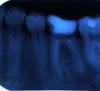

lavina Опубликовано 26 июля, 2012 Поделиться Опубликовано 26 июля, 2012 (изменено) Здравствуйте!Пять лет назад мне лечили шестерку слева снизу. Пломбировали каналы, пломбу поставили очень большую, фактически от зуба остались тонкие стенки невысокие, только корень, а сверху он был нарощенный. Врач сказала, что со временем поставите штифт.Все эти пять лет он не болел, совсем никак себя не проявлял.В мае этого года зуб откололся, и я пошла к протезисту. Сделали снимок, оказалось, что под зубом воспаление, каналы плохо пролечены.Мне всего 25 лет, поэтому зуб терять не хотелось, мне предложили попробовать его перелечить. Меня сразу предупредили: есть шанс, что зуб не поддастся лечению. Неделю ходила с лекарством в каналах (первые пару дней зуб побаливал, потом перестал). Каналы закрыли, на снимке было видно, что воспаление существенно сократилось, но до конца не прошло. Врач сказала, что оно долго развивалось, поэтому за неделю не пройдет (это правда?). Зуб не беспокоил.Пойти к протезисту получилось через несколько недель. Пришлось сделать новый снимок, на котором он увидел гнойники под корнем зуба. Сказал, что гарантий дать не сможет, так как при любой простуде или промоченных ногах зуб может дать о себе знать, а может и не дать. Я согласилась делать коронку.На первом посещении мне просверлили отверстия для штифтов. После этого зуб начал немного ныть, но не сильно и не постоянно. Через неделю поставили металлическую вкладку (не знаю как правильно назвать) и временную коронку. На следующий день зуб стал болеть. На него больно надавливать даже верхними зубами, не то, что жевать. Под ним стала болеть десна. Причем болит как то совсем внизу (где щека соединяется с десной). Сегодня зуб уже почти не болит. Даже жевать могу на нем, но боль в десне осталась.Я сделала снимок. Извините за качество, по другому не получается.(На первом снимке зуб со штифтом, на втором еще до лечения)Может, штифт установлен неправильно? Подскажите, что можно сделать? Теперь только удаление? Вроде каналы были перелечены хорошо, что пошло не так? Возможно ли это от того, что не сразу пошла ставить коронку? Изменено 26 июля, 2012 пользователем lavina Ссылка на комментарий

doktorSergey Опубликовано 26 июля, 2012 Поделиться Опубликовано 26 июля, 2012 Зуб к сожалению придется удалять- в корне перфорация- дырка в кость. Если сейчас не удалить- кость будет рассасываться, и потом имплантат туда поставить будет затруднительно, и соседние зубы могут ослабиться. Ссылка на комментарий

lavina Опубликовано 26 июля, 2012 Автор Поделиться Опубликовано 26 июля, 2012 То есть, как я понимаю, штифт поставили неправильно? Ссылка на комментарий

doktorSergey Опубликовано 26 июля, 2012 Поделиться Опубликовано 26 июля, 2012 То есть, как я понимаю, штифт поставили неправильно?Угу. Ссылка на комментарий